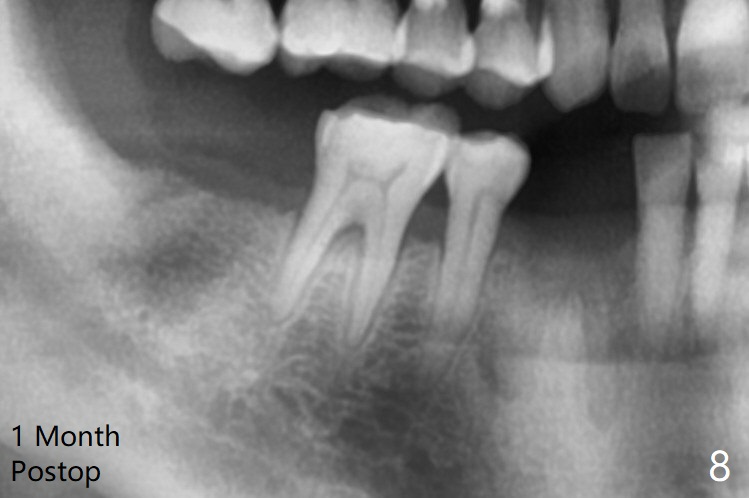

拔除32号牙时发现它接近31区(将要植牙),必须植骨(近中部分(远中塞入胶原塞)),27,28颊侧骨板缺失(大量肉芽组织),植骨理所应当,而且必须拼命推压,但愿推到颊侧骨板,细的皮质骨没有压制感,非要加入粗的松质骨皮质骨,一张12x12毫米胎盘膜剪成两片覆盖27/28和32拔牙窝,4-0 PGA缝线固定,拍摄术后半侧全景片后(图二 (*:骨粉)),使用牙周敷料保护伤口。27/28重叠,近远中8.11毫米,可以植入一个植体,做悬臂桥,或者植入两者之间。The bone graft remains in place 1 month postop (Fig.8).  术后一个月27,28号牙位骨粉保持原位(图八)。